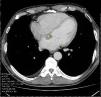

A 57-year-old man was referred to the hospital for evaluation of a right hilar lung mass discovered on a chest X-ray performed because of a persistent cough, increasing effort dyspnea and deterioration of the general condition. He has no medical history and had smoked 35 packs a year. On the admission, physical examination showed a slow heart rate at 40 beats per minute. The electrocardiogram showed a complete atrioventricular block. On echocardiography, a 26×17mm mass was noted in the basal area of the atrial septum without interfering with the mitral valve function (Fig. 1). A thoracic computed tomography (CT) scan revealed a right pulmonary hilum mass with mediastinal and peritoneal lymphadenopathy, adrenal metastasis, and a low-density mass located on the interatrial septum (Fig. 2). Fiberoptic bronchoscopy showed stenosis with mucosal tumor infiltration in the right upper lobe bronchus. The bronchial biopsy revealed a moderately differentiated adenocarcinoma. Based on these findings, the atrioventricular block was associated with interatrial septum metastasis of the lung adenocarcinoma. A pacemaker was implanted and pemetrexed platinum chemotherapy was started.